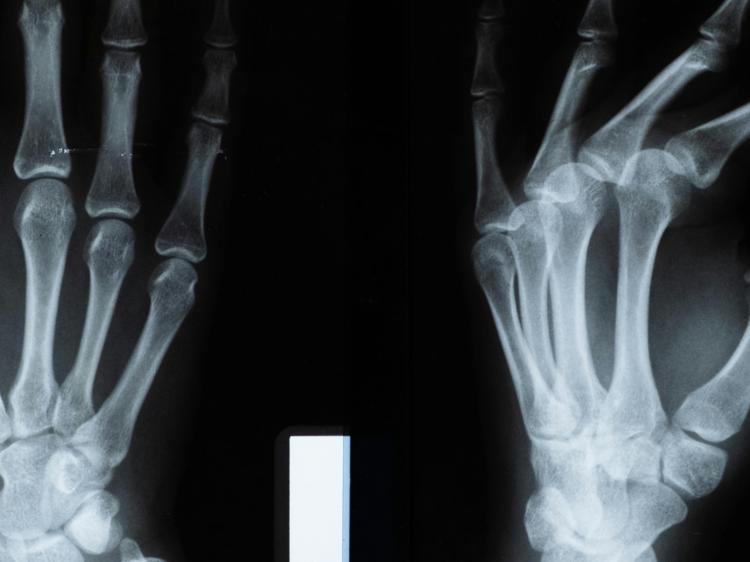

骨骼是人体的“支架”,偶尔会摸到其表面有突起或包块,不少人会担心是不是严重问题。其实从临床数据看,85%的骨性包块都是良性的,主要可以分成三大类常见情况。

二、天生的“骨头凸起”——生理性骨突

有些部位本来就有正常的骨性凸起,比如手腕外侧的桡骨茎突、胯部前方的髂前上棘,属于个体发育差异。这类包块有三个特点:

- 低风险:先观察 如果包块小于2厘米、不疼也不影响活动,拍片看没变化,每6个月拍次X线就行。